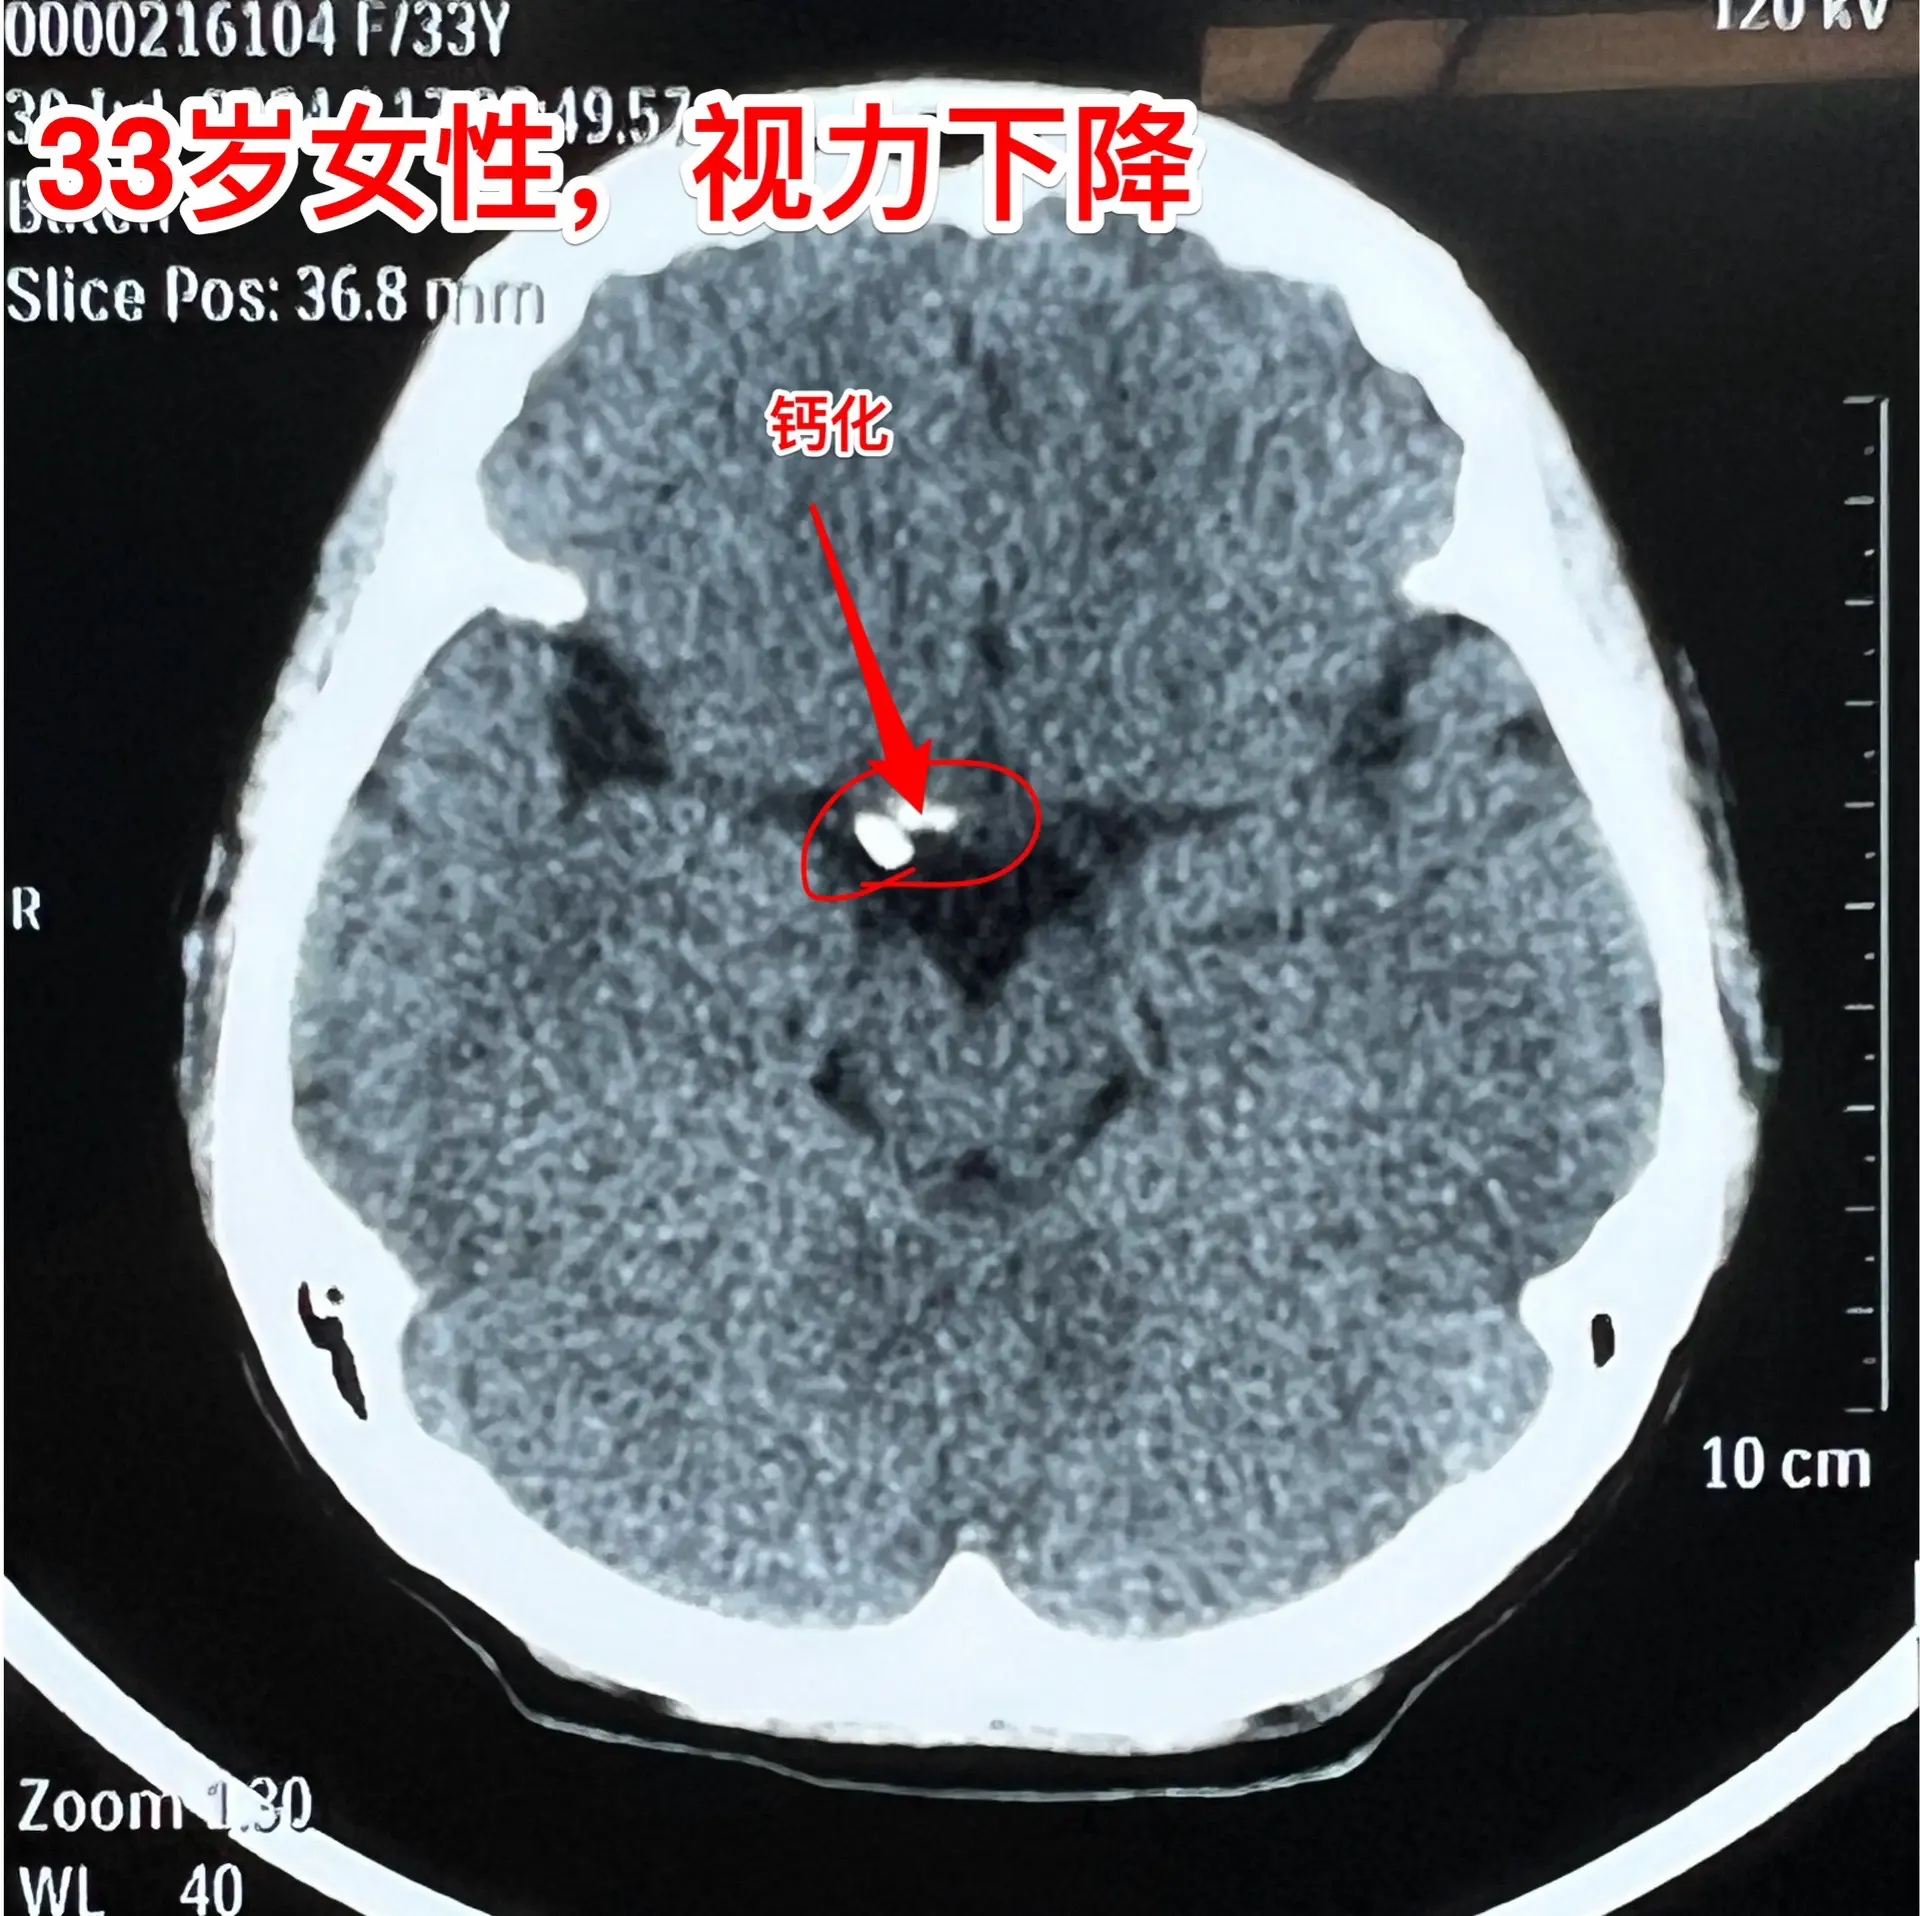

33岁医护人员患颅咽管瘤,压力大不大?33岁潍坊市女性,医护专业人员。因右眼视力下降到医院去检查,发现脑部长了肿瘤。从影像学资料可以看出这是典型的颅咽管瘤。 病人33岁了,还未婚未育,除了视力下降之外基本没有感觉自己得病。得知自已患颅咽管瘤后她的心理压力大不大? 从她的外观看她似乎没有太多压力,面容总是带微笑的!她其实很有压力,担忧作了手术后会不会影响生育,当然也担忧肿瘤会不会复发。 9月5日为她作了手术,颅咽管瘤得到完全切除,垂体柄保留了70%。 手术后她清醒过来看见我,第一句话就问:会不会影响生育?我说:生育还是很有希望的,一步一步来。(这是我科今年的第132个颅咽管瘤病例)